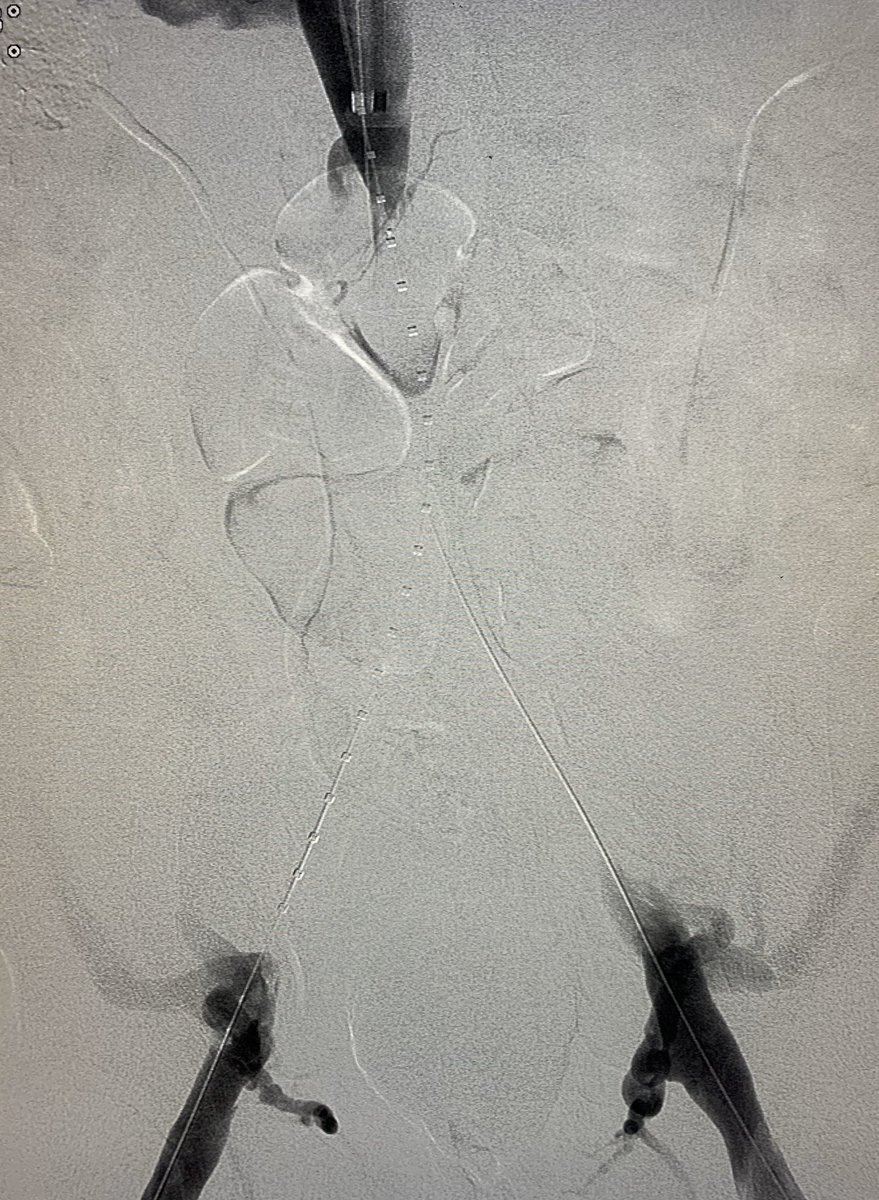

SVC syndrome from Type 4, chronic , CTVO with h/0 lung malignancy EBRT. CT shows both Innominate, SVC occlusion with extensive chest wall collaterals. Done with conscious sedation although prefer GA.

@SIRspecialists@SIR_ECS@JVIRmedia@AVIRnews#irad#Occlusion#SVC@EVTodaypic.twitter.com/iJGNmgePEJ